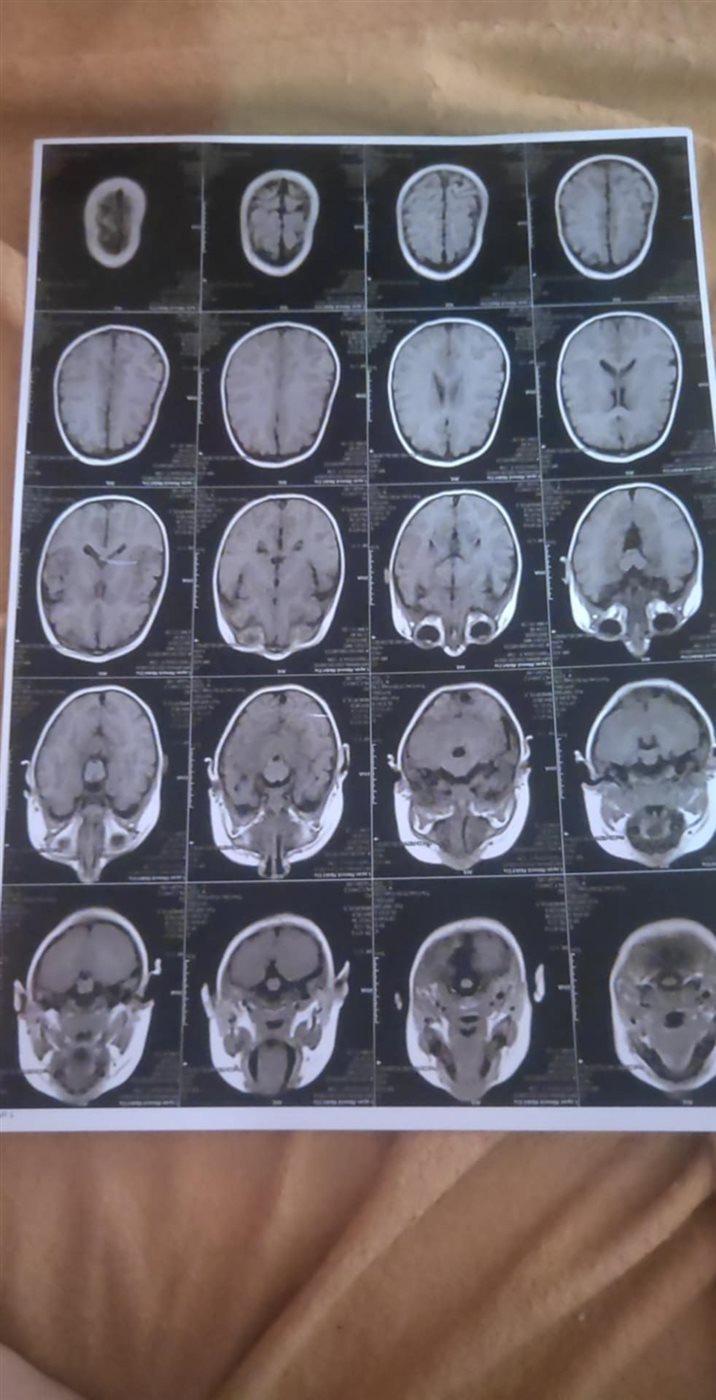

وقالت والدة الصغيرة: ليان عندها ضمور في المخ بـ الخلايا السابعة، ودايمًا بيجلها تشنجات ونوبات صرع، وبعد التحليل الجيني طلع عندها مرض نادر اسمه متلازمة ريت، ومحتاجة علاج جيني، ليان حالتها تعبانة ومحتاجة تدخل عاجل.